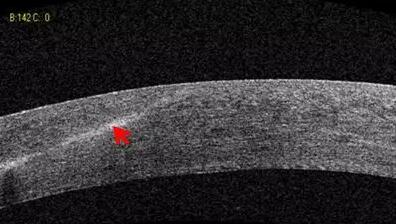

1:OCT 前节断层扫描可识别出巩膜突、Schwalbe 线 、Schlemm 管 等结构,且辨识度很高,巩膜突(78.9%)、Schwalbe线(93.3%),若对图像进行放大查看, 更佳。